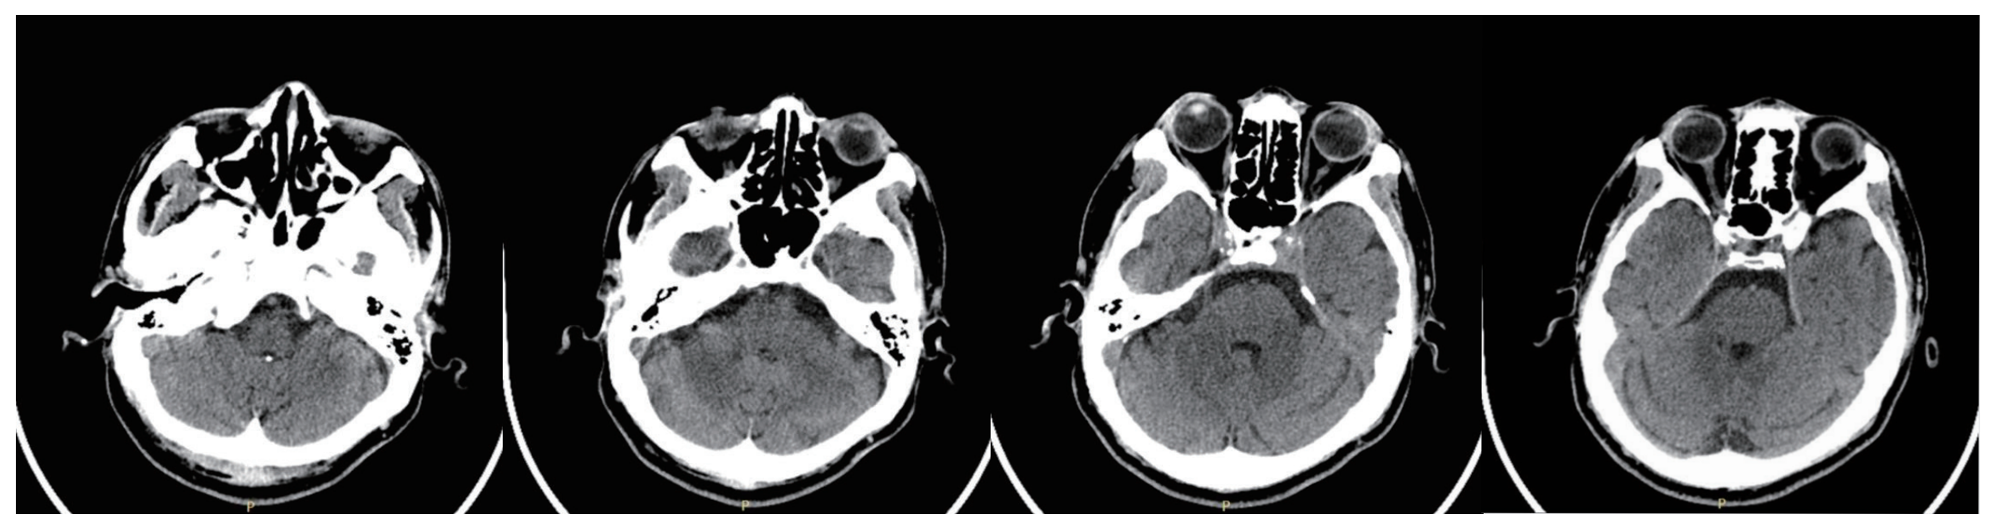

Skull

The quality of CT images is significantly improved by effectively reducing artifacts caused by metal implants and greatly upgrading the image clarity of the tissue structure surrounding the metal implants.